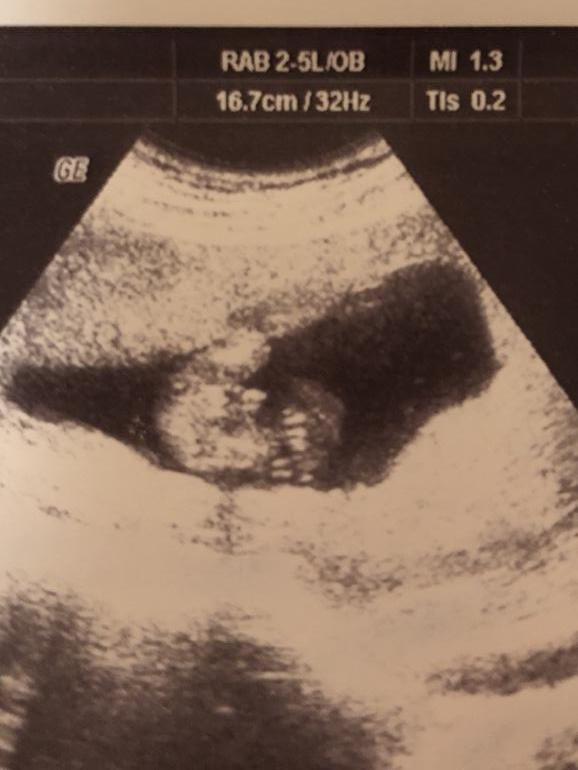

Определение пола 17 недель

Вопросы про УЗИ, обследования и анализы: что, где, как, когда?Была на узи в 12 недель, сказали точно мальчик. На узи в 14 недель другому врачу виделась девочка. Пойду в 17 недель, скажут наконец точно? Что думаете? В 17 уже хорошо видно?У меня тонус и низкая плацентация, поэтому на узи часто хожу.